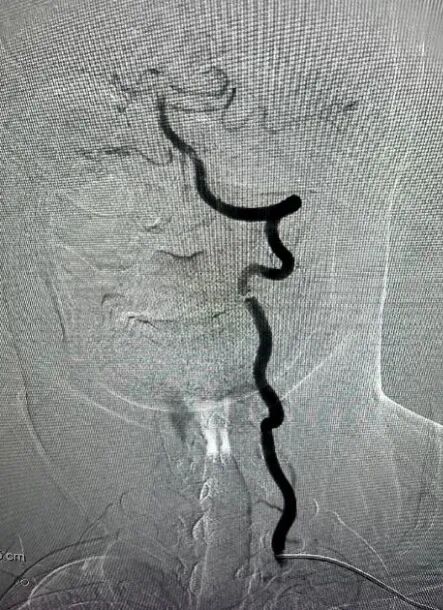

1.置入5F桡鞘,并完成血管造影,明确病变为栓塞

什么叫桡鞘【桡径通神】一例低NIHSS评分,基底动脉闭塞经左桡动脉取栓_https://www.jmylbn.com_新闻资讯_第12张

什么叫桡鞘【桡径通神】一例低NIHSS评分,基底动脉闭塞经左桡动脉取栓_https://www.jmylbn.com_新闻资讯_第13张